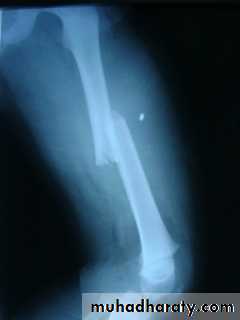

Femoral shaft fracture

This fracture occurs at any age, it is common especially in young adults, and usually results from a high energy injury, such as

( car accident , fall from height).

X-ray :

Shows the type of fractures, and displacement. The x-ray should include the hip and knee and x-ray of pelvis to avoid missing segmental fractures, knee injuries, fractures of neck of femur, dislocation of hip, fractures of acetabulum and pelvis.